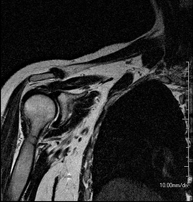

- RM d'Espatlla

Exploració per a l'estudi de lesions en els tendons, els músculs i les articulacions. La seva principal utilitat resideix en diagnosticar les lesions dels tendons del braçal rotatori. Té una durada aproximada de 20 minuts. No utilitza radiació ionitzant. - RM de Braç

Exploració per a l'estudi de les lesions en petites estructures anatòmiques de l'articulació que solen lesionar-se en pacients que pateixen luxació o inestabilitat crònica. L'estudi ve precedit per una injecció de contrast a l'interior de l'articulació, realitzada sota control de raigs X. La durada total dels dos procediments és de 50 minuts. - Artro-RM de Canell